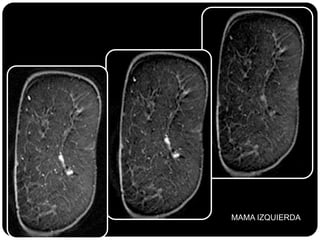

Paciente femenina de 66 años con historia clínica de 1er gesta antes de los 30 años y antecedentes de lactancia positiva, presenta una lesión palpable en la mama derecha. Los estudios radiológicos indican un diagnóstico de bi-rads 5, con biopsias revelando adenocarcinoma lobulillar infiltrante en la glándula mamaria derecha y adenocarcinoma ductal in situ en la izquierda. El caso fue evaluado por las doctoras Jacqueline Preciado Vargas y Beatriz E. González Ulloa.